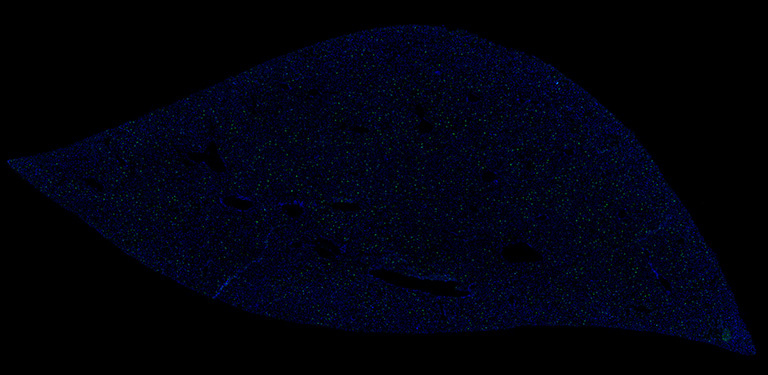

This image depicts an injured liver that is in the process of initiating regeneration by producing proteins that tells the cells to grow. With the goal of better understanding how an organism senses organ injury to induce regeneration, the researcher used RNA FISH to identify the cell type responsible for growth factor synthesis following liver injury. The image reveals that hepatic stellate cells are responsible for growth factor synthesis, indicating that the liver senses its own injury to induce regeneration.